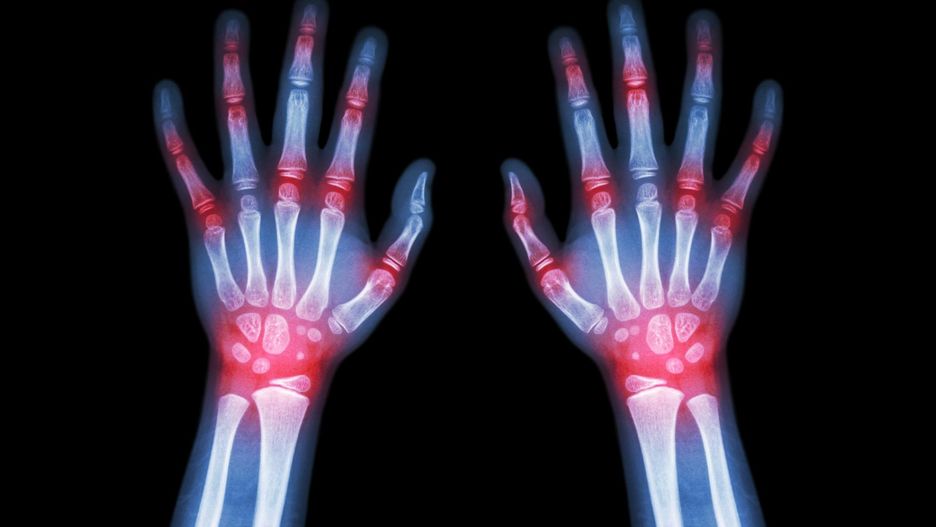

Bóle stawów Badania opublikowane w Clinical Journal of Pain mówią, że bóle stawów nasilają się w porze zimowej. W zimie mamy znacznie mniej słonecznych chwil, a słońce to najlepsze naturalne źródło witaminy D.

Mniej witaminy D zwiększa stan zapalny, a to z kolei potęguje ból związany z chorobą zwyrodnieniową stawów. Zapalenie pęcherza, na dolegliwości pęcherza w zimie narażone są szczególnie kobiety.